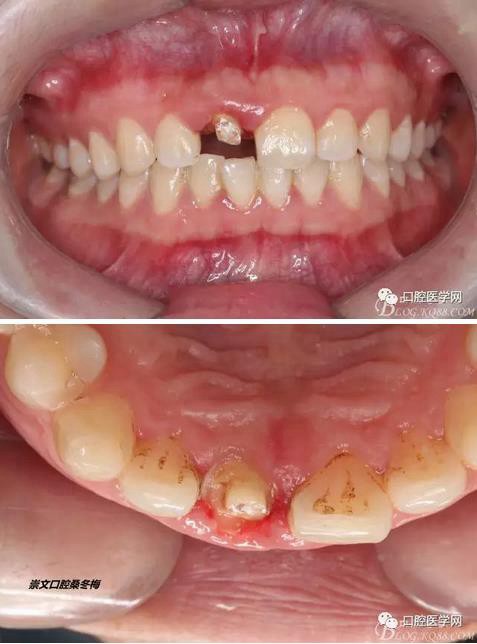

術(shù)前口內(nèi)照,11殘根,唇側(cè)牙齦紅腫,肩臺(tái)在齦下2毫米,舌側(cè)正常.21有被動(dòng)萌出,長(zhǎng)寬比例不協(xié)調(diào)。口腔衛(wèi)生一般,有菌斑。

術(shù)前原有牙冠復(fù)位,牙齦紅腫。